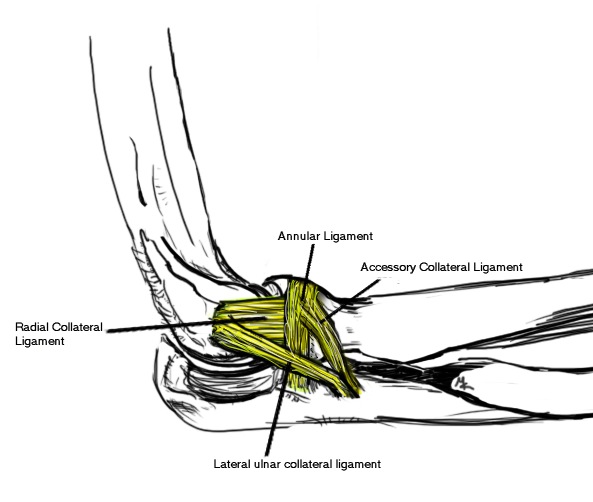

Anatomy LCL

Radius rotates externally in relation to the ulna

- posterior displacement of the radial head relative to the capitellum

- in flexion